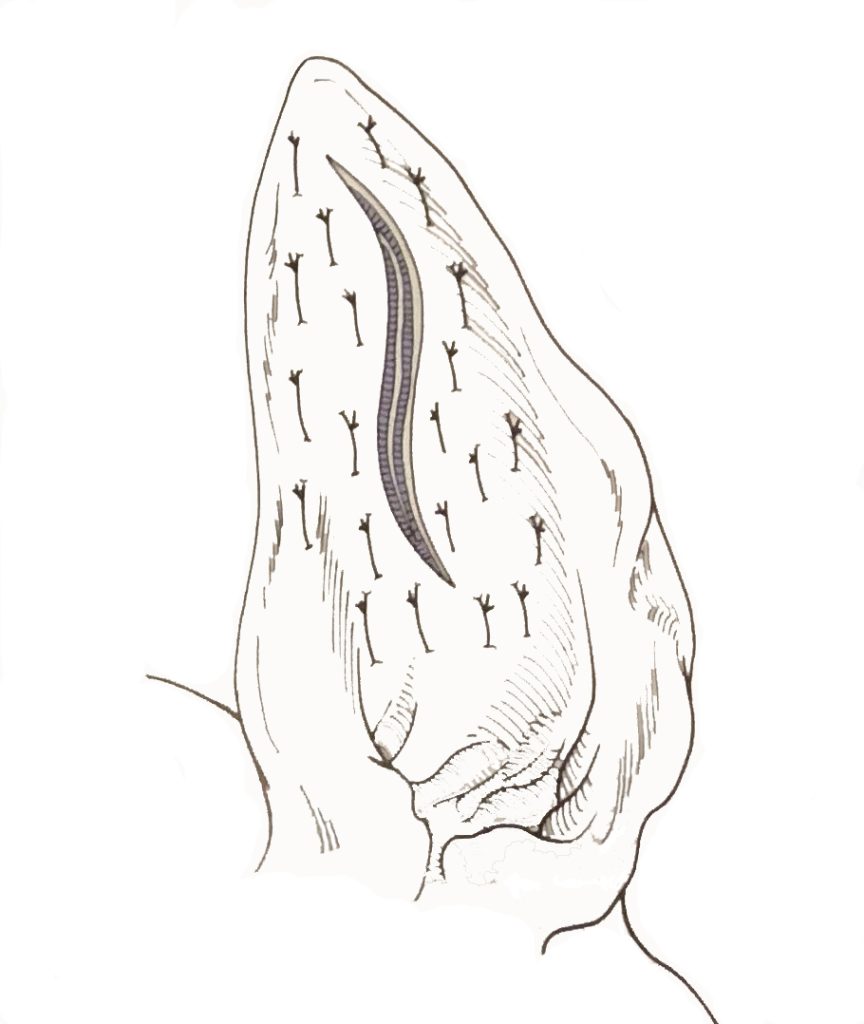

De eerste behandelmethode is een operatie. Hierbij wordt de oorschelp geopend, het bloed en stolsels worden verwijderd en vervolgens wordt de huid vastgehecht aan het kraakbeen. Het wondje dient open gelaten te worden zodat het bloed eruit kan. Het duurt een paar dagen voor het wondje gesloten is. Meestal is het oor na ongeveer 3-4 weken geheel hersteld.